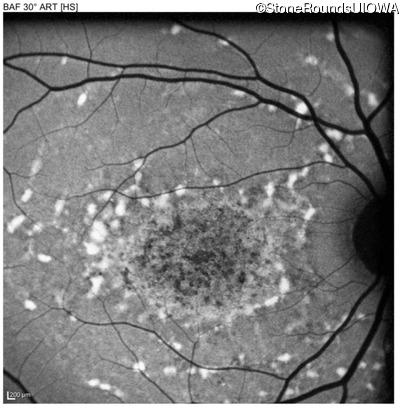

Age at visit: 22 years

OD OS

Age at visit: 17 years

Age at visit: 18 years

Age at visit: 19 years